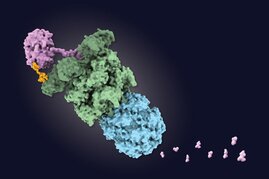

Das Hepatitis-E-Virus (HEV) ist weit verbreitet, und bisher gibt es kein wirksames Medikament. Auf der Suche danach sind die sogenannten Rocaglamide…